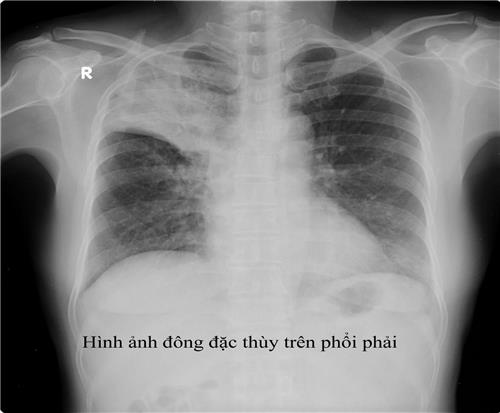

- Xquang phổi thường quy: hình ảnh trên phim X-quang gợi ý lao phổi tiến triển là thâm nhiễm, nốt, hang, có thể 1 bên hoặc 2 bên. Ở người có HIV, hình ảnh X-quang phổi ít thấy hình hang, hay gặp tổn thương tổ chức kẽ và có thể ở vùng thấp của phổi. X-quang phổi có giá trị sàng lọc cao với độ nhạy trên 90% với các trường hợp lao phổi AFB(+). Cần tăng cường sử dụng X-quang phổi tại các cơ sở y tế cho các trường hợp có triệu chứng hô hấp để sàng lọc lao phổi. Tuy nhiên cần lưu ý độ đặc hiệu không cao, nên không khẳng định chẩn đoán lao phổi chỉ bằng 1 phim X-quang phổi. Xquang phổi còn có tác dụng đánh giá đáp ứng với điều trị thử bằng kháng sinh thông thường trước khi chẩn đoán lao phổi không có bằng chứng vi khuẩn và để đánh giá kế quả điều trị lao sau 2 tháng và kết thúc điều trị.

Chẩn đoán xác định: lâm sàng: cấp tính với các triệu chứng ho, sốt cao, khó thở, có thể tím tái. X-quang phổi có nhiều nốt mờ, kích thước đều, đậm độ đều và phân bố khắp 2 phổi (3 đều: kích thước, mật độ và đậm độ cản quang các hạt kê trên phim X-quang phổi). Xét nghiệm đờm thường âm tính. Ngoài ra xét nghiệm vi khuẩn trong các mẫu bệnh phẩm (dịch phế quản, dịch não tủy, máu) có thể dương tính.